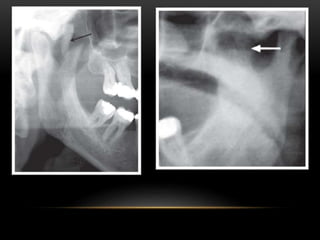

The calcified cartilage is located on a lateral view within the

pharyngeal air space inferior to the greater cornu of the

hyoid bone and adjacent to the superior border of C4. The

superior cornu of a calcified thyroid cartilage appears

medial to C4 and is superimposed on the prevertebral soft

tissue.

Ossified thyroid and cricoid cartilages in a 40-year-old female patient

demonstrated on a lateral cephalometric radiograph.